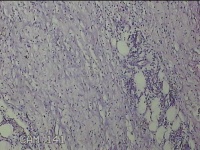

右侧腋下结节

性别

男

年龄

56岁

临床诊断

一般病史

标本名称

大体所见

灰白粉红色组织2.3x2x0.8cm一块,表面带梭形皮肤2.3x2cm,皮下见结节2x1cm一个,结节部分已切开,见结节呈囊性,囊内有少许灰白色角化物,囊壁厚0.1cm。

炎性病变。